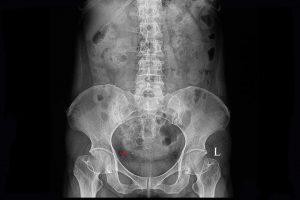

L’hématurie, qu’elle soit visible à l’œil nu ou uniquement au microscope, constitue unsymptôme à ne pas négliger. Derrière cette présence de sang dans les urines peuvent secacher des pathologies bénignes comme des affections plus graves, notamment tumorales.Le rôle de l’imagerie médicale est alors central, tant pour identifier l’origine du saignementque...